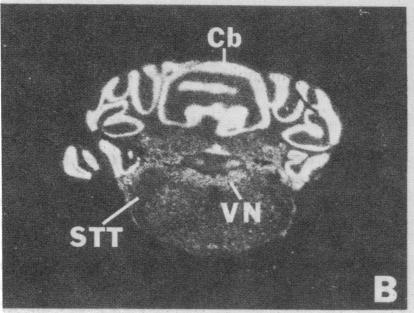

Brain src protooncogene is expressed in two forms, one identical to message in other tissues, and one containing an 18-nucleotide insert specific to brain. We have mapped mRNA for the two forms of src in rat brain with selective antisense oligonucleotide probes to the brain (src+) and peripheral (src-) forms. Fetal rat src mRNA levels were much higher in the central nervous system than any peripheral organ. In adult brain, src+ mRNA level was highest in the internal granular layer of the olfactory bulb, pyramidal cells of the hippocampus, granule cells of the dentate gyrus, and cerebellar granule cells. src+ and src- levels were similar in hindbrain, but src+ levels were higher than those of src- in forebrain. These distributions suggest that src+ may play roles in a number of neural processes, possibly including neuronal plasticity.

脑源原癌基因以两种形式表达,一种与其他组织中的信使核糖核酸相同,另一种含有特定于脑的18个核苷酸的插入片段。我们用针对脑(src+)和外周(src-)形式的选择性反义寡核苷酸探针,在大鼠脑中绘制了两种src形式的信使核糖核酸图谱。胎鼠src信使核糖核酸水平在中枢神经系统中比任何外周器官都高得多。在成体脑中,src+信使核糖核酸水平在嗅球的内颗粒层、海马体的锥体细胞、齿状回的颗粒细胞和小脑颗粒细胞中最高。src+和src-水平在后脑中相似,但src+水平在前脑中高于src-。这些分布表明src+可能在许多神经过程中发挥作用,可能包括神经元可塑性。